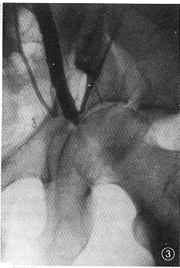

图3,4 男,43岁,车祸致骨盆骨折12 h。图3为左髂外动脉造影,见动脉中断、断端呈锥状。图4示髂外动脉断端内对比剂向左股内侧弥散,髂内动脉造影示股动脉依靠侧支循环供血。诊断为髂外动脉断裂,血栓形成,股动脉侧支循环建立